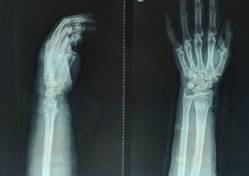

手法复位小夹板固定治疗骨折

优点:免于开刀之苦。